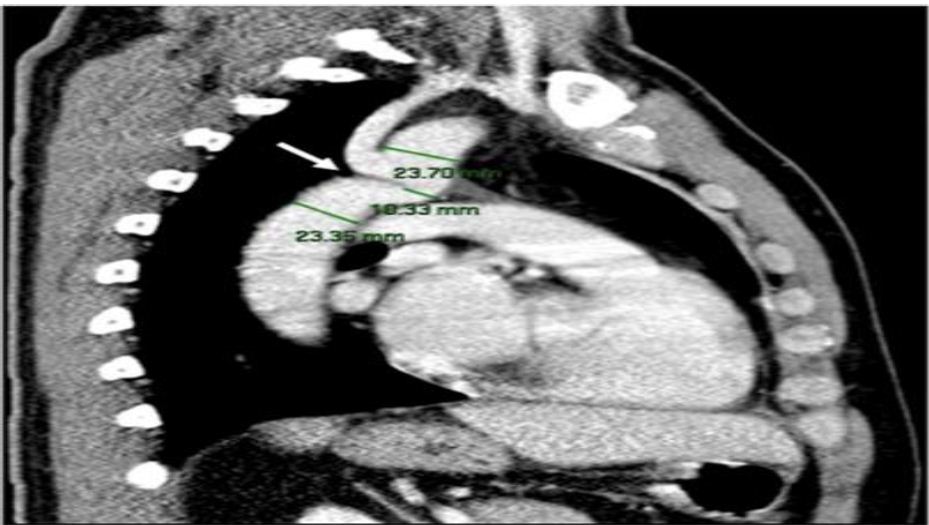

Se complementó con una angiotomografía mostrando un calibre de 3.6 cm en la salida del ventrículo izquierdo y mostrando posterior al nacimiento de la arteria subclavia izquierda una disminución del calibre en un 40% para posteriormente recuperar su calibre normal (Figura 1 y 2).

Figura 1. Reconstrucción sagital de tomografía contrastada de tórax donde se observa el área de coartación de la aorta (Flecha) junto con las dimensiones en los diferentes segmentos.